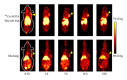

Molecular imaging is an emerging field that integrates advanced imaging technology with cellular and molecular biology. It can realize noninvasive and real time visualization, measurement of physiological or pathological process in the living organism at the cellular and molecular level, providing an effective method of information acquiring for diagnosis, therapy, and drug development and evaluating treatment of efficacy. Molecular imaging requires high resolution and high sensitive instruments and specific imaging agents that link the imaging signal with molecular event. Recently, the application of new emerging chemical technology and nanotechnology has stimulated the development of imaging agents. Nanoparticles modified with small molecule, peptide, antibody, and aptamer have been extensively applied for preclinical studies. Therapeutic drug or gene is incorporated into nanoparticles to construct multifunctional imaging agents which allow for theranostic applications. In this review, we will discuss the characteristics of molecular imaging, the novel imaging agent including targeted imaging agent and multifunctional imaging agent, as well as cite some examples of their application in molecular imaging and therapy.